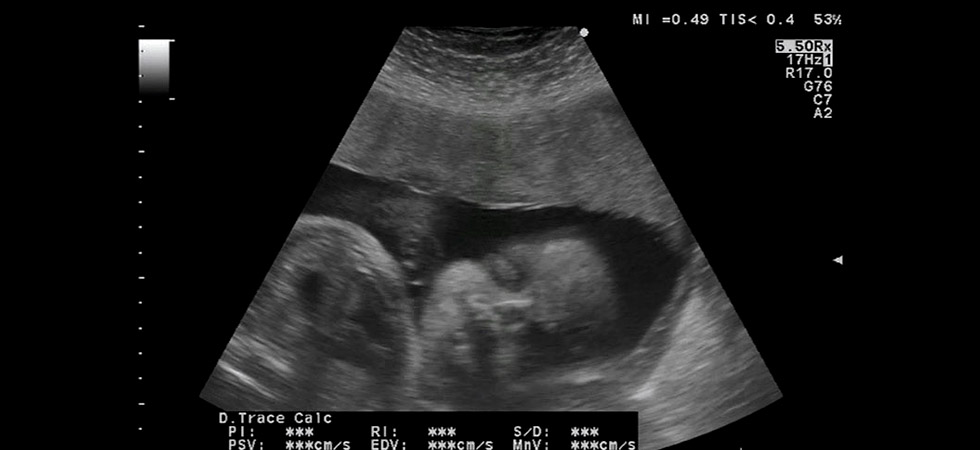

Фото УЗИ на 38 неделе беременности

УЗИ

УЗИ на 38 неделе беременности может проводиться разве что по каким-то особым показаниям, ведь, по идее, три плановых ультразвуковых исследования женщиной уже пройдено. Но, если все же требуется уточнить, например, расположение плода в матке, исключить обвитие пуповиной, оценить степень зрелости плаценты, врач может посчитать за необходимое еще одно УЗИ на сроке в 38 недель.

Как и до этого, при проведении УЗИ специалист осмотрит не только малыша, но и состояние матки. Интерес при обследовании представляет размер малыша и соотношение отдельных частей его тела между собой, частота сердцебиения крохи, его положение в матке.

Во время ультразвукового исследования оценит врач также и количество, качество околоплодных вод, исследует структуру и размер, степень зрелости плаценты. Интерес представляет также зрелость шейки матки, ее размеры и состояние в целом.